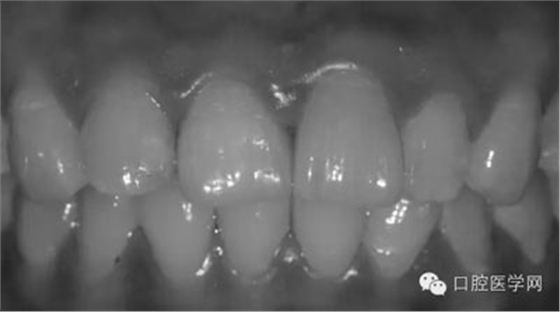

1、術(shù)前比色照

將比色照飽和度調(diào)到最低有助于牙齒明度的選擇

將比色照的飽和度調(diào)到最高有助于牙齒道飽和度選擇